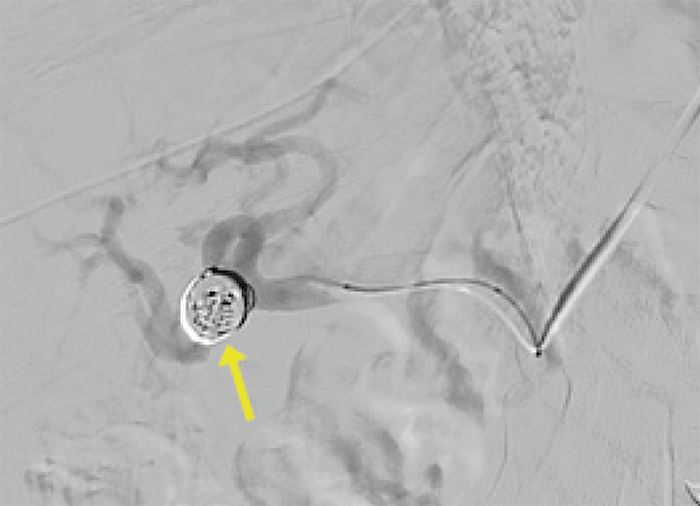

Figure 6. Completion Angiogram Demonstrating Coils and Distal Blood Flow to Right Lobe of Liver. Published with Permission

Completion angiogram demonstrated the coils in the HAA with preservation of flow in the distal right hepatic artery, maintaining blood flow to the right lobe of the liver (Figure 6). Following the procedure, the patient's symptoms resolved completely. LFTs remained normal throughout her stay. CT exam seven months after her procedure demonstrated the coil embolization in the previously present RHA aneurysm, and the patient remains asymptomatic 18 months later.